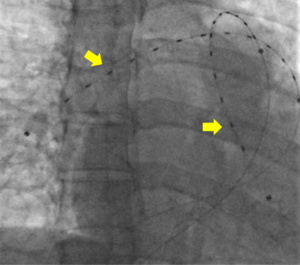

Though no data exists regarding the use of catheter directed pulmonary arterial thrombolysis in pregnancy, the presumed risks were speculated to be lower than that of systemic thrombolysis. Anticoagulation alone was also considered. The dangers of RV dysfunction in the setting of the hemodynamic challenge of pregnancy and upcoming delivery were weighed carefully (7). After assessing the risks and benefits of the available options for both the mother and fetus, the team reached a consensus to proceed with CDT using an ultrasound-enhanced EKOS catheter (Figure 2). The goal was to minimize risks to the mother and fetus and simultaneously optimize RV recovery (7,8).

This multi-disciplinary organization was orchestrated within 30 minutes of the PERT activation and through a single PERT group conference call. With this planning in place, the patient was brought to the catheterization lab for placement of bilateral EKOS catheters. Via these catheters, she was treated with 12 mg of tPA over 5 hours. Prior to removal of the catheters, she was noted to have a decrease in her PA systolic pressures from 50 mmHg at the time of the procedure to 32 mmHg at 5 hours. No maternal complications or fetal distress occurred during or after the procedure. She was discharged on enoxaparin (1 mg/kg twice daily) on post-procedure day 3. Repeat echocardiogram performed 2 weeks after her hospitalization demonstrated normalization of her right ventricle (Figure 3). The infant was delivered without complications at 39.5 weeks, and the patient and infant continue to do well.